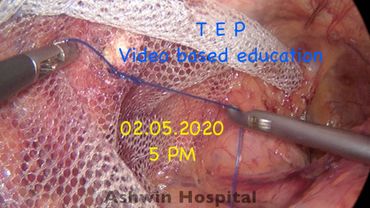

TEP - video based education